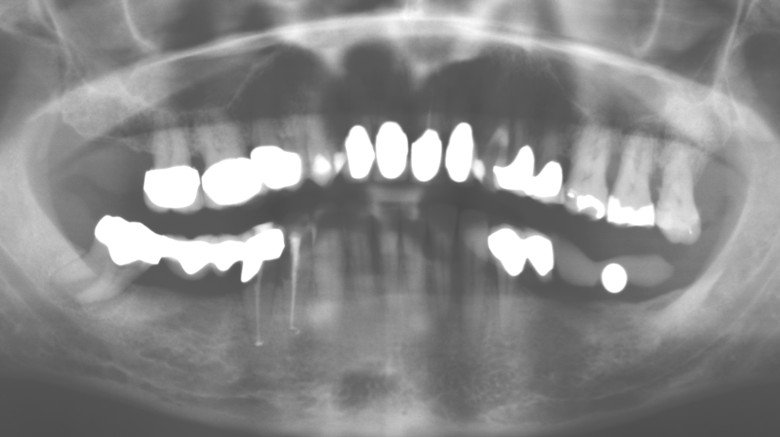

Due to the presence of periodontal disease, SPT was performed every three months in the first years following the insertion. The patient demonstrated a high degree of motivation and good compliance. The pocket depths recorded annually revealed a stable periodontal situation with a BOP index of below five per cent. On the basis of the stable periodontal situation and good cooperation on the patient’s part, the recall interval was extended to every six months as of the sixth year of the prosthetic function phase. Following the change in the recall interval, the respective annual documentation of the periodontal status continued to reveal a stable periodontal situation with no increase in the pocket depths and a BOP index below five per cent (Fig. 2a and b).

Fig. 2: The pocket depths recorded annually with six-monthly SPT display no increasing trend and a BOP index of below 5 per cent with a largely inflammation-free periodontal situation. a) PERIO status in 2011 (after five years with implants). b) PERIO status in 2016 (after ten years with implants).